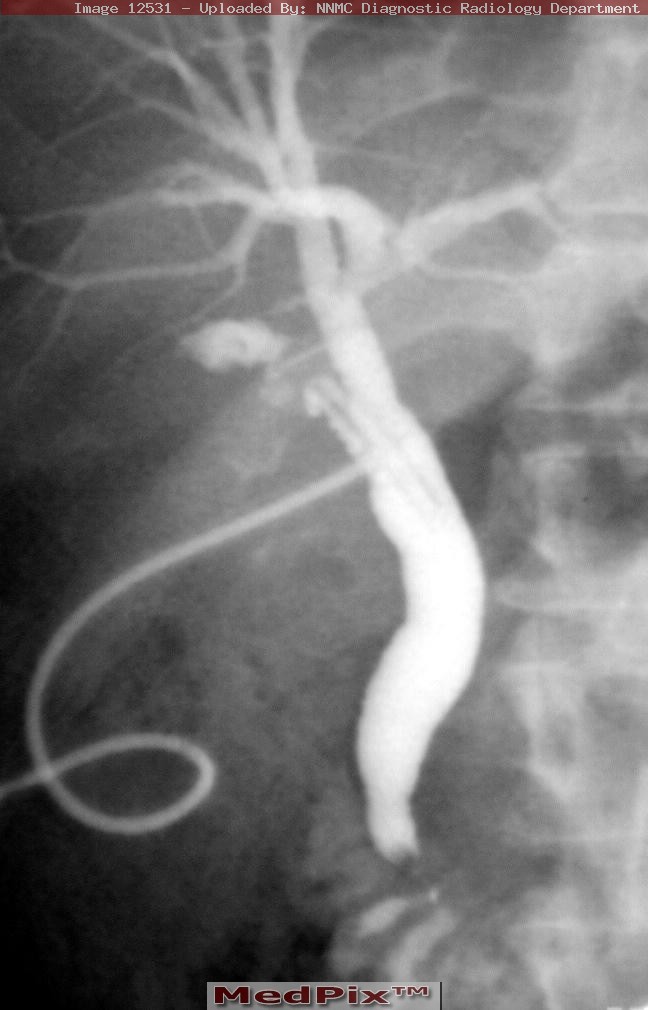

Fluoroscopy - Cholangiogram

Fluoroscopy is a study of moving body structures--similar to an X-ray "movie." A continuous X-ray beam is passed through the body part being examined. The beam is transmitted to a TV-like monitor so that the body part and its motion can be seen in detail. Fluoroscopy, as an imaging tool, enables physicians to look at many body systems, including the skeletal, digestive, urinary, respiratory, and reproductive systems.

A cholangiogram is a special x-ray procedure that is done with contrast dye to visualise the bile ducts. The bile ducts drain bile from the liver into the duodenum (first part of the small bowel).

This examination will demonstrate the bile duct and its branches to see if there are gallstones or tumour present.

In the procedure, the contrast medium is injected into the body and a series of x-rays are taken to reveal any abnormalities.